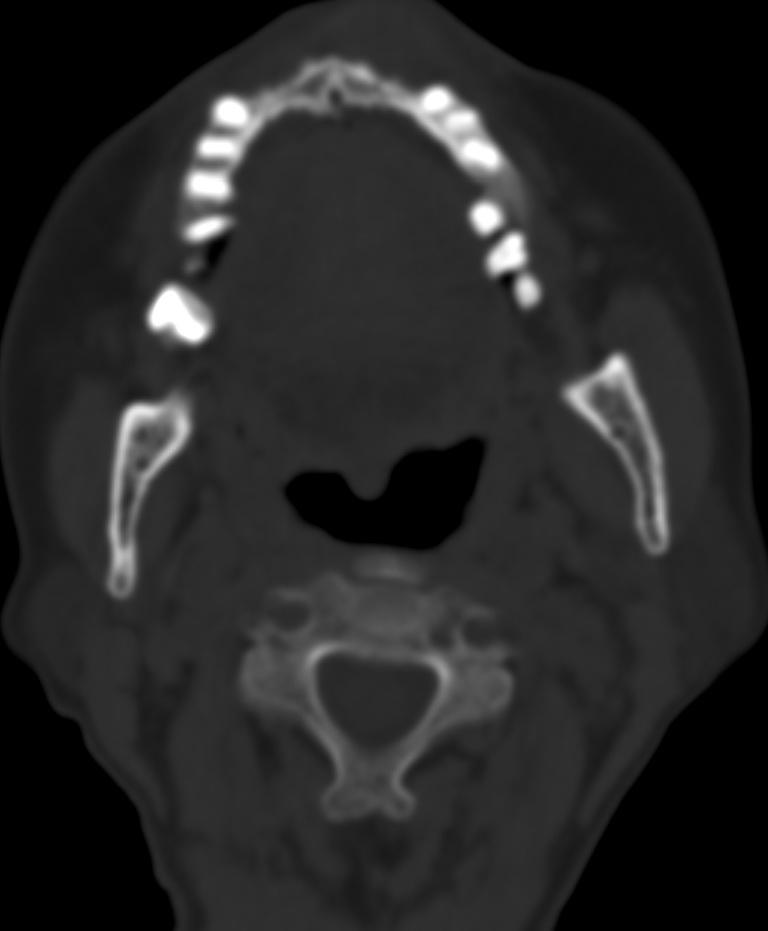

女,68岁。发现上唇无痛性肿块2年多,查体局部皮肤隆起,其余未见异常。

病灶ct值约42hu。